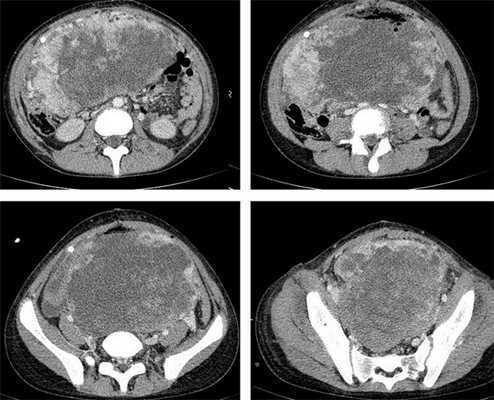

Яичники

Овариальные (расположенные в яичниках, яичниковые) опухоли наиболее часто проявляются болью в животе. При осмотре пальпируется опухоль в малом тазу, часто - в брюшной полости. Также за счет асцита (скопления в брюшной полости жидкости) увеличен живот. Нередко у девочек с таким диагнозом бывает лихорадка.

Самая часто диагностируемая герминогенная опухоль - это дисгерминома. Преимущественно ее обнаруживают во второй декаде жизни. У маленьких девочек встречается редко. Такое заболевания сравнительно быстро распространяется, поражая брюшину и второй яичник. Обычно новообразования односторонние, имеют большие размеры. В связи с этим частое явление - разрыв капсулы новообразования.

- УЗИ. «Ультразвук» нужен для того, чтобы выявить первичный очаг как гонадной (в половых органах), так и внегонадной герминогенной опухоли. Его также проводят в ходе терапии, чтобы оценить ее эффективность.

- КТ (расшифровка: компьютерная томография), МРТ (расшифровка: магнитно-резонансная томография), ПЭТ-КТ (расшифровка: позитронно-эмиссионная томография, совмещенная с КТ). Эти обследования необходимы, чтобы рассмотреть структуры организма послойно и визуализировать опухоль. Они показывают, как сильно распространен патологический опухолевый процесс на находящиеся рядом ткани и органы, есть ли поражение костей. КТ - это самый чувствительный метод для обнаружения метастазов в легких. Проведение МРТ и КТ головного мозга необходимо, чтобы обнаружить и визуализировать герминогенные новообразования эпифиза.

Рисунок 8. КТ органов брюшной полости - на снимках вы можете увидеть опухоль яичника.

Особенности течения заболевания определяются локализацией, размером и степенью злокачественности неоплазии. Типичными симптомами герминогенных опухолей яичника являются боли в животе различной интенсивности в сочетании с нарушениями менструального цикла. У детей последний признак отсутствует, что обуславливает отсутствие настороженности в отношении поражения внутренних половых органов на начальных стадиях заболевания. При прогрессировании герминогенных опухолей к перечисленным симптомам присоединяются увеличение живота и нарушения мочеиспускания. При пальпации на начальных стадиях определяется округлый, умеренно подвижный узел с четкими контурами. В последующем узел увеличивается в размере, возникают увеличение и деформация живота. На поздних стадиях выявляется асцит и нарушения функций различных органов, обусловленные отдаленным метастазированием.

Компьютерная томография органов грудной клетки, брюшной полости, малого таза используются для оценки распространения опухолевого процесса (рис.5).

При дооперационном обследовании, и обязательно при высоком уровне ХГ или множественных метастазах в лёгкие, прибегают к МРТ головного мозга с контрастированием. В головном мозге при распространённом процессе могут существовать бессимптомные метастазы. Необходима КТ от шеи до малого таза, что позволяет выявить опухолевые отсевы и целенаправленно их разыскивать при операции, или вообще отказаться от операции в пользу химиотерапии при метастатическом поражении лёгких.